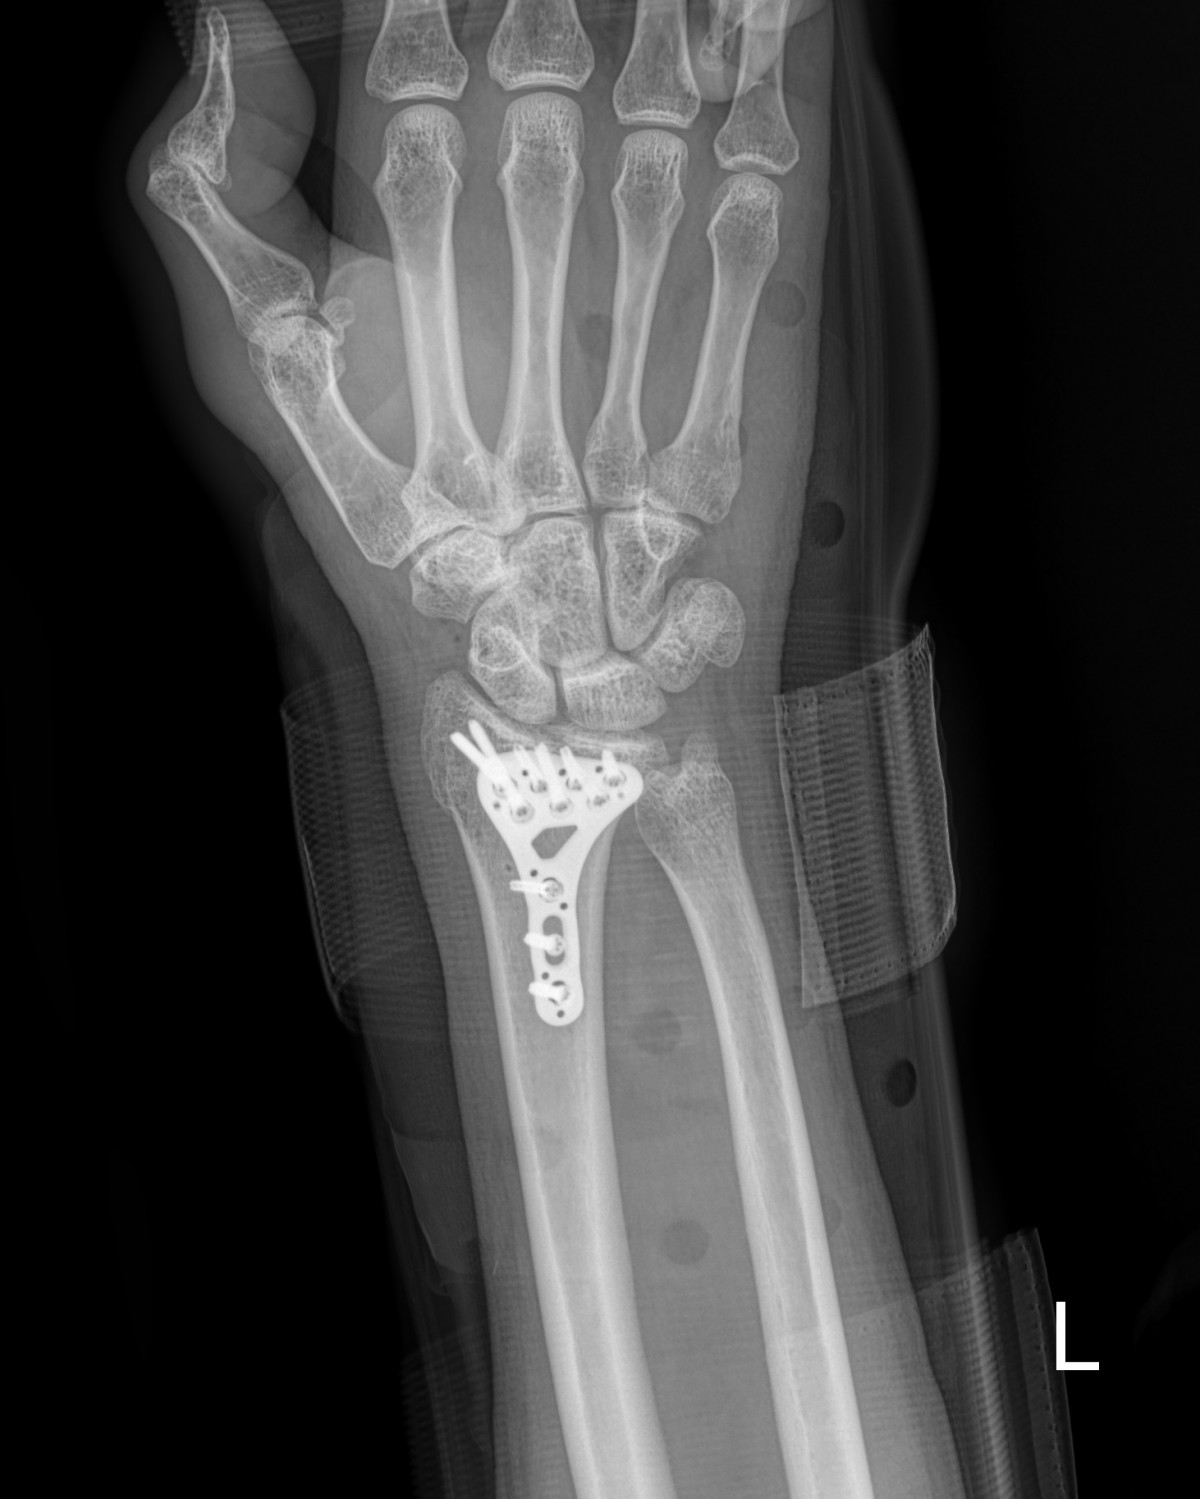

정지영원장님 손목 골절 수술 김리O 환자

작성자 최고관리자 댓글 0건 조회 817회 작성일 25-05-19 15:31

99e29187067a0bd925a1108e8520daf8_1747636264_86.jpg

99e29187067a0bd925a1108e8520daf8_1747636276_8534.jpg